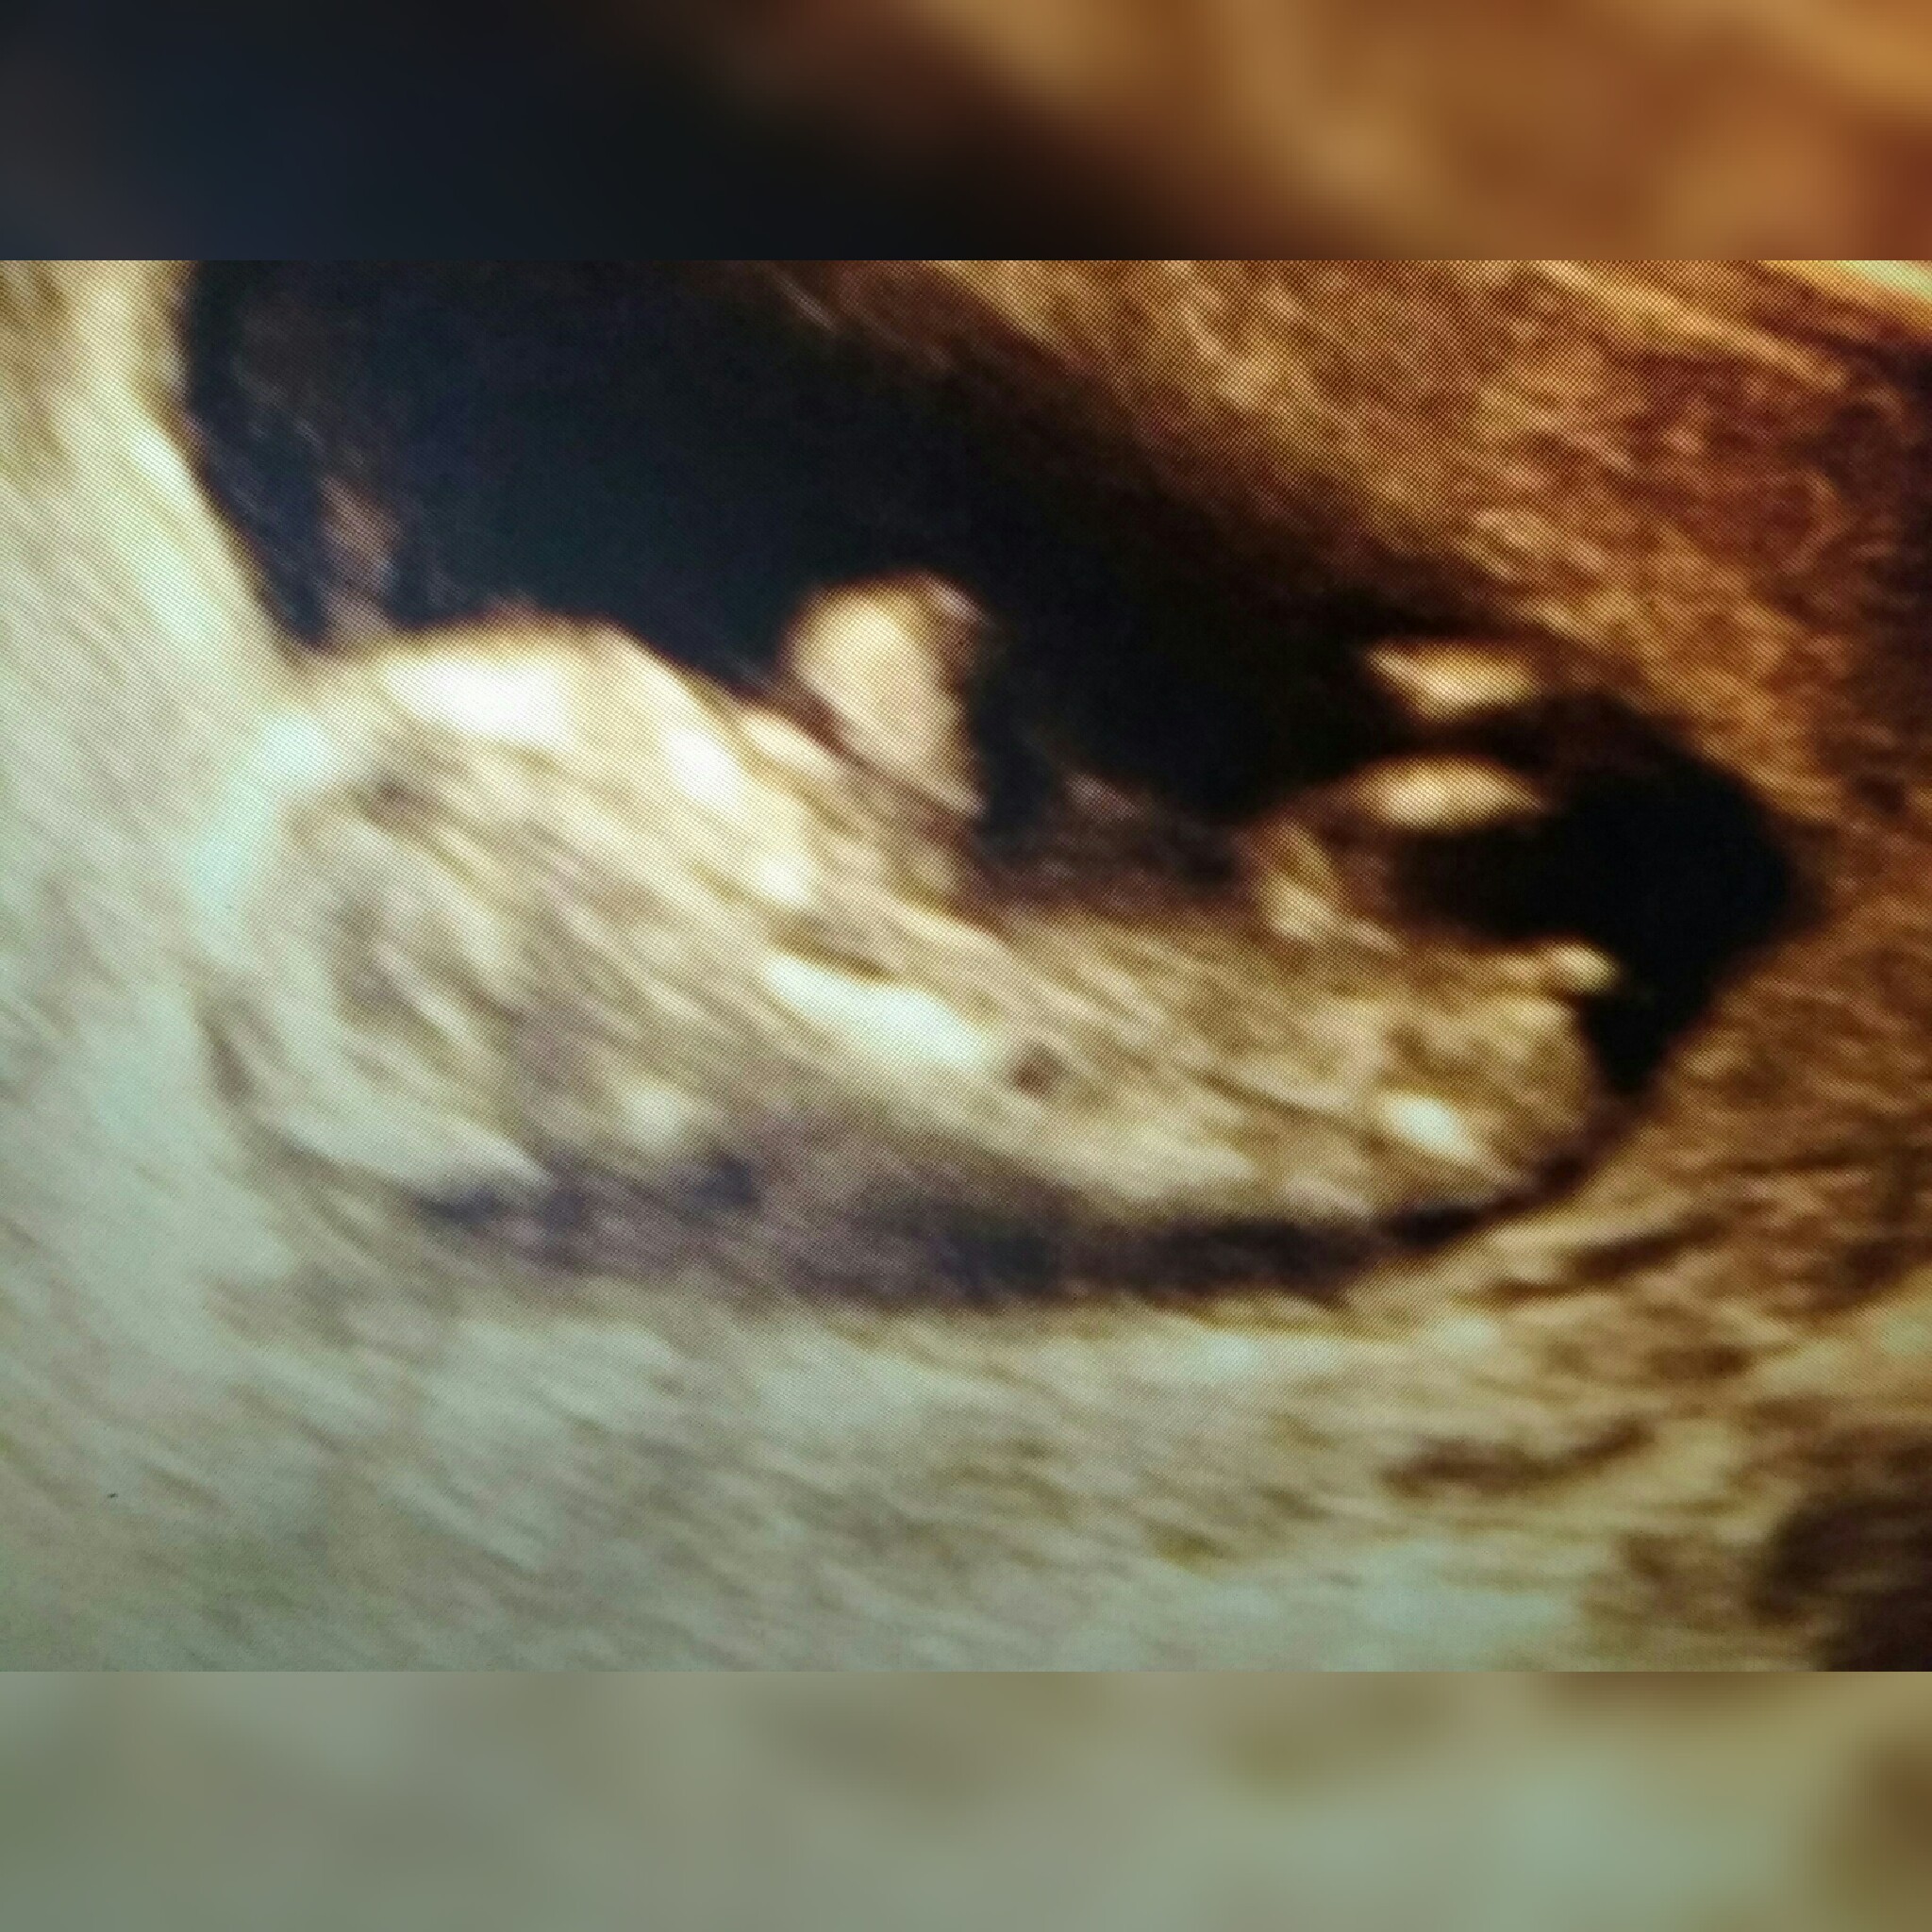

Witam w 19 tygodniu ciąży dowiedziałam się ze będę miała dziewczynkę w 20 tyg okazało się jednak , że to chłopak. Sama już nie wiem bo na jednym usg widać na pewno dziewuche a na drugim chłopca. Może to pempowina ?? Może ktoś mi pomoże rozwiązać ta zagadkę

• 4A8F5FF1-76CA-4DE0-AC12-5EDF08E820F2.jpg

4A8F5FF1-76CA-4DE0-AC12-5EDF08E820F2.jpg

596,4 KB · Wyświetleń: 23 764